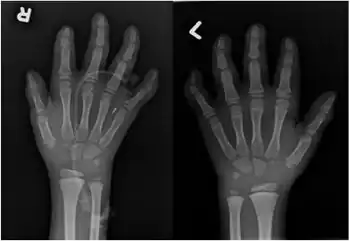

Hyperphosphatasia with mental retardation syndrome, HPMRS,[1] also known as Mabry syndrome,[2] has been described in patients recruited on four continents world-wide.[3] Mabry syndrome was confirmed[4] to represent an autosomal recessive syndrome characterized by severe mental retardation, considerably elevated serum levels of alkaline phosphatase, hypoplastic terminal phalanges, and distinct facial features that include: hypertelorism, a broad nasal bridge and a rectangular face.

The clinical diagnosis can be established if the patient has repeatedly elevated levels of alkaline phosphatase activity in the blood serum and exhibits intellectual disability. Supportive for the clinical diagnosis are epilepsies, brachydactyly and a characteristic facial gestalt, which can also be assessed by means of AI.[10]